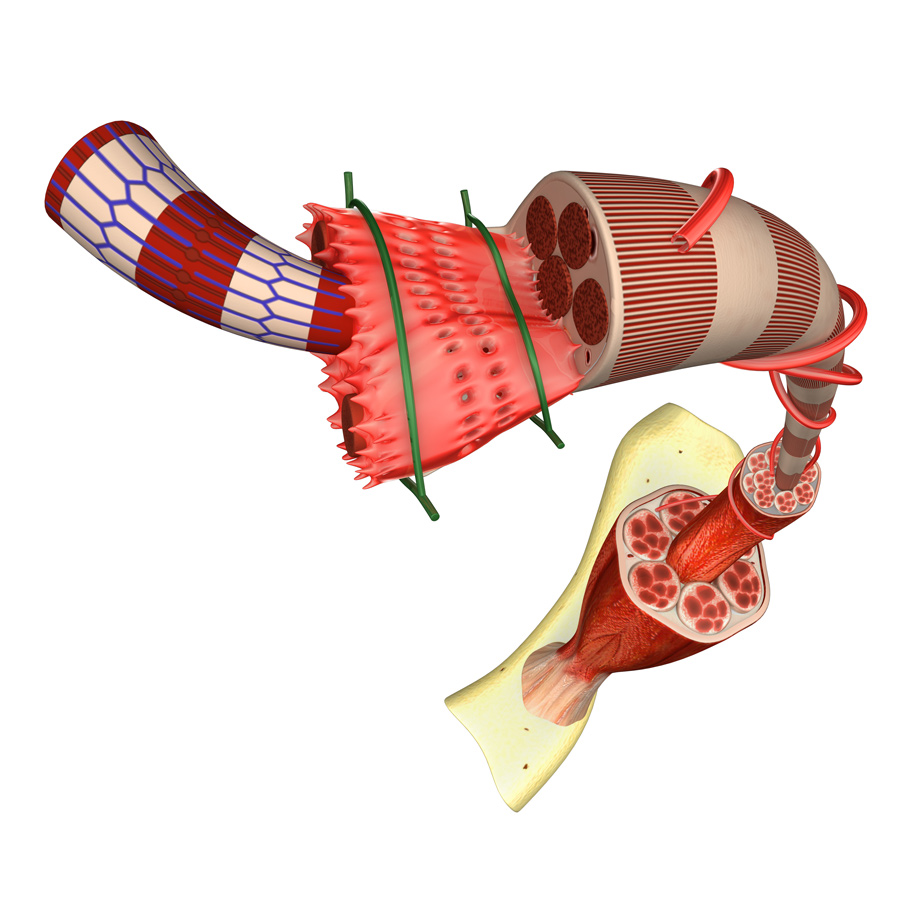

通常情况下,骨骼肌(即附着在骨骼上的肌肉)在受伤后具有显著的自愈能力。肌肉干细胞,特别是一种被称为卫星细胞的细胞,在愈合过程中起着至关重要的作用。因此,研究人员将卫星细胞作为治疗肌肉萎缩症的潜在途径。利用老鼠进行的研究已经产生了有希望的结果,移植的卫星细胞可以恢复肌营养不良和更好的肌肉功能。对DMD患者的研究已经开始;然而,在这成为一种广泛使用的治疗方法之前,还需要做更多的工作。

当干细胞生长时在体外,它们产生新肌肉的能力就会减弱。研究人员发现,干细胞需要一个非常特殊的环境才能充分发挥它们的潜能在体外和在活的有机体内,即在肌肉中。了解环境如何影响肌肉干细胞,如果这种治疗和疾病建模的方法正在进行中,这是至关重要的。

帮助肌肉干细胞的一种策略保持其有用的特性在体外就是在细胞表面涂上一种能模拟正常环境的物质。这种物质可以包含其他类型的肌肉细胞,或生物材料——人造物质,用以与生物系统相互作用。

另一种方法是实际创造人工肌肉在体外,利用卫星细胞和其他肌肉细胞结合细胞外基质。用这种方法产生的肌肉组织可以部分恢复受损肌肉的功能。和干细胞一样,它也可以作为研究疾病进展的有用模型。